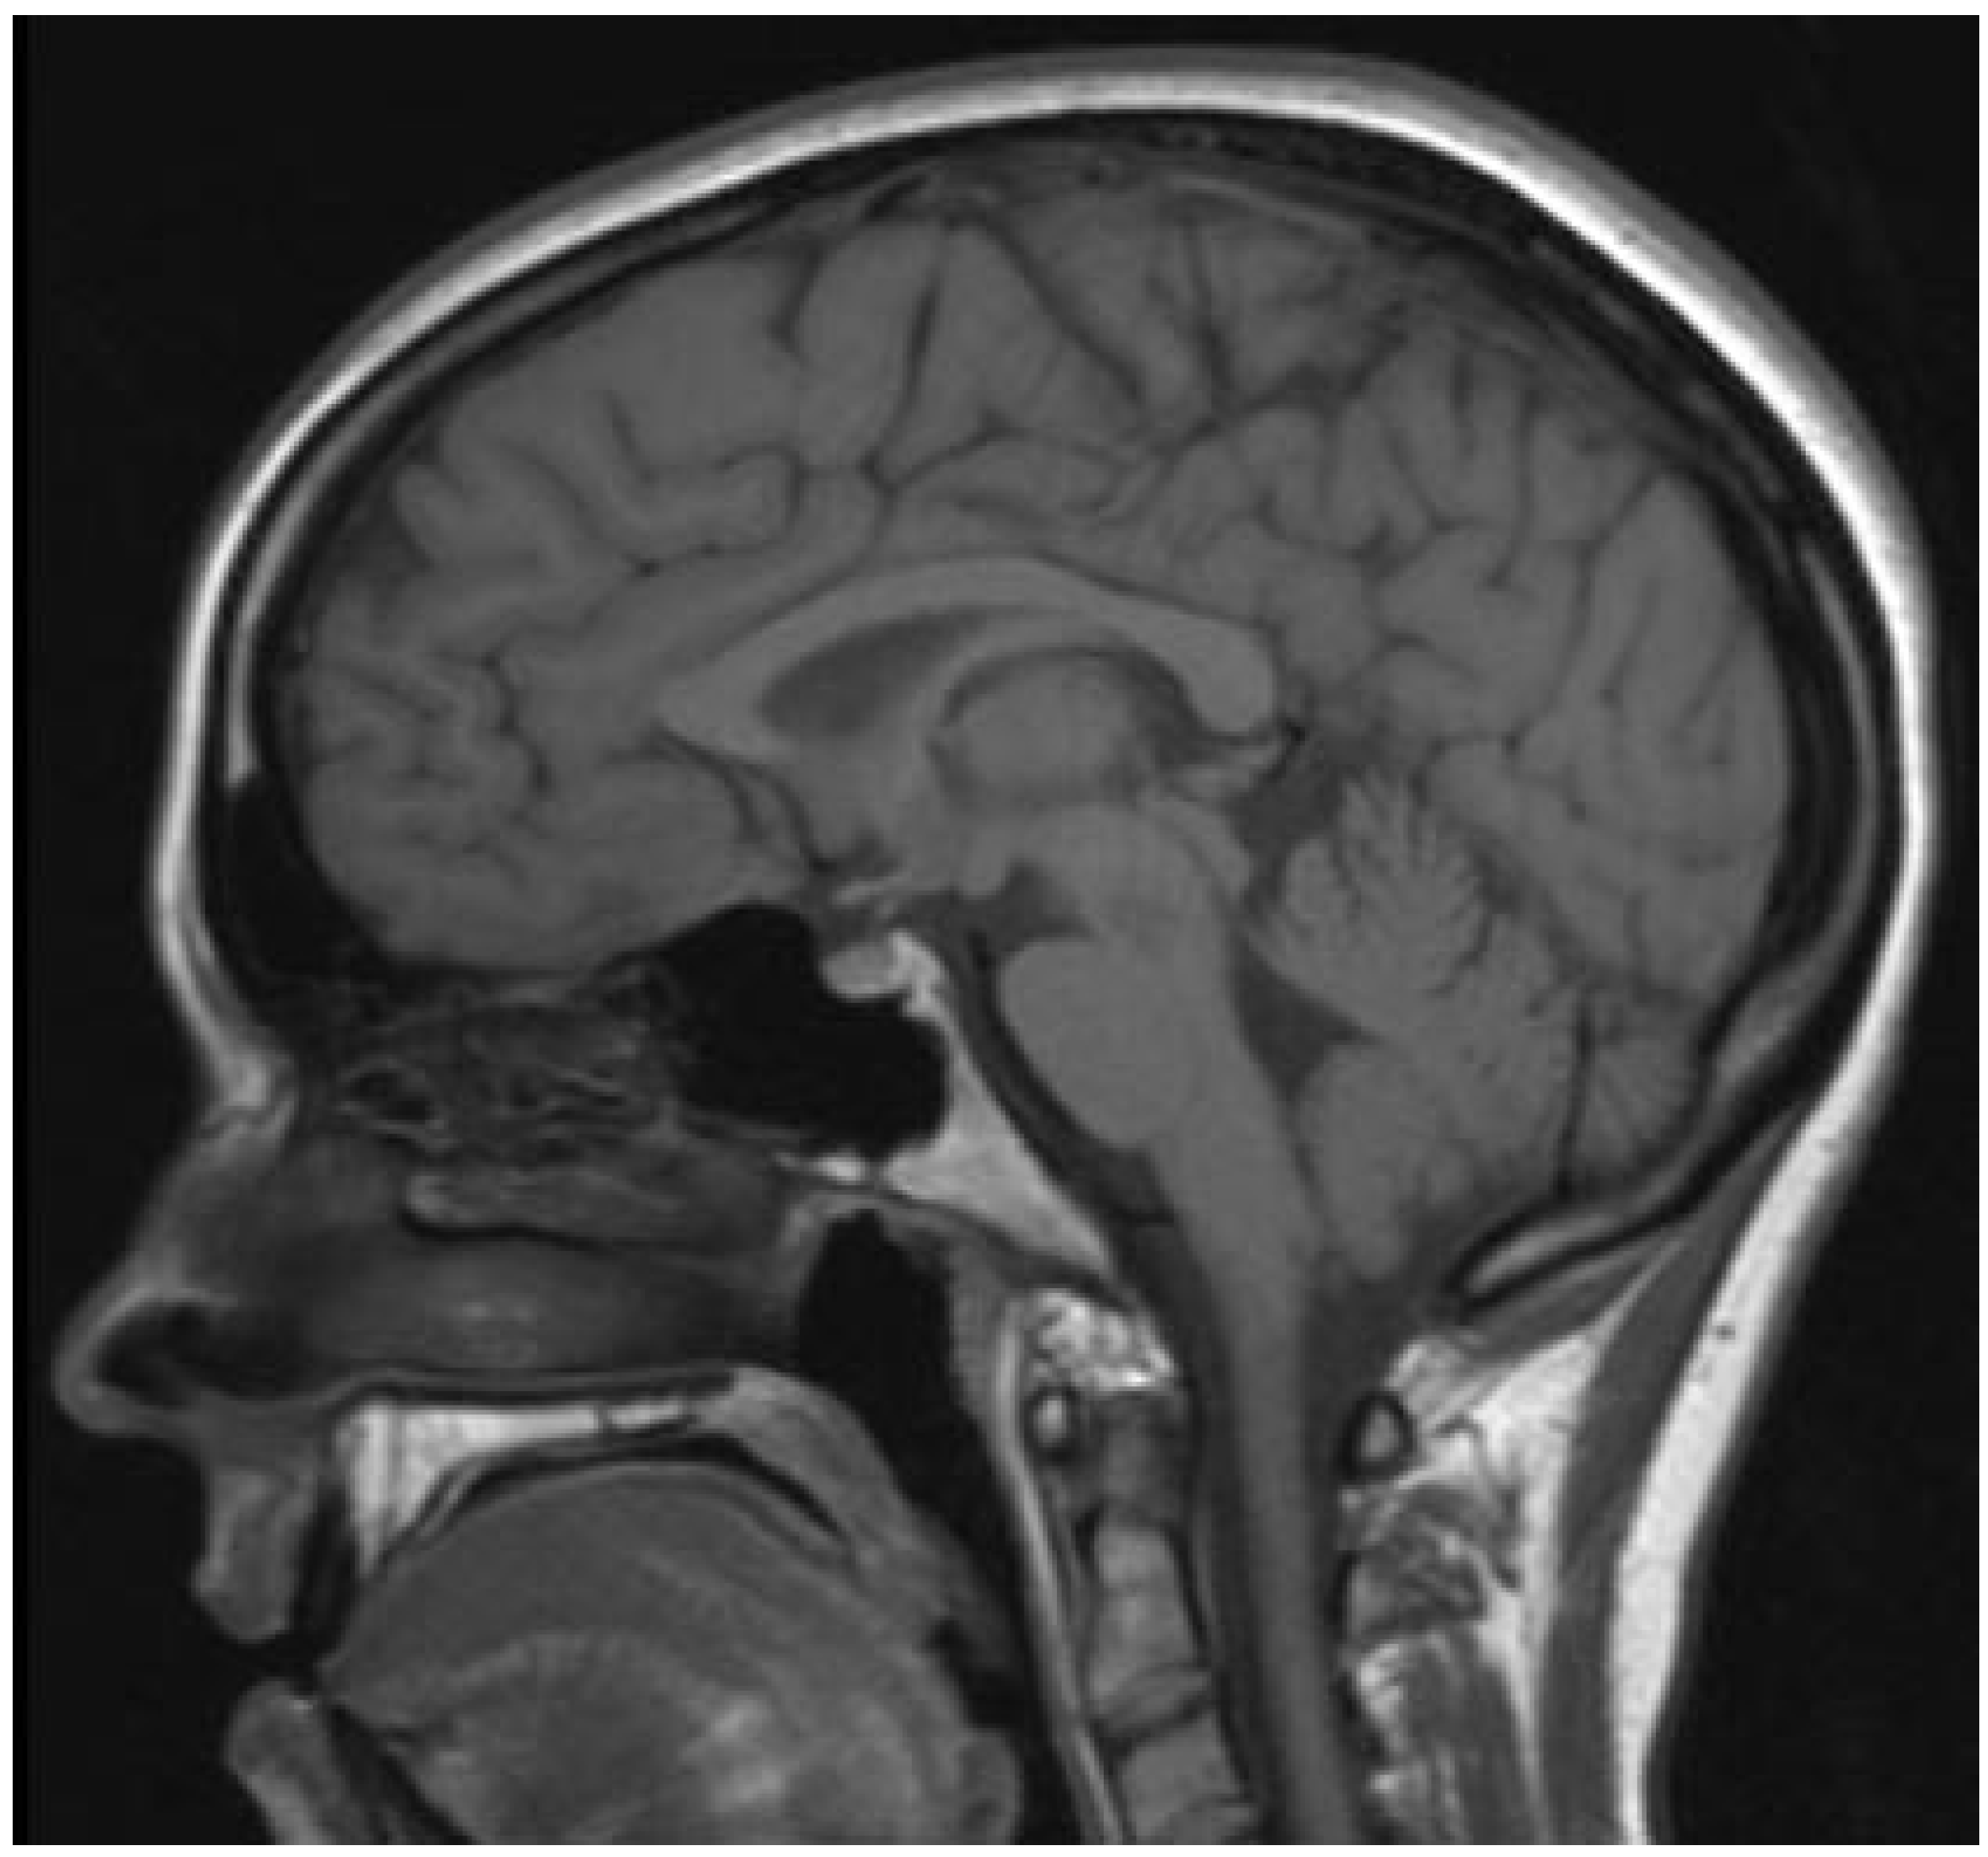

Table 1 represents the running time for three images from well-known image dataset [11] (Figure 1, Figure 2 and Figure 3).

Figure 1. MRI image of the Brain. Params—421 × 392, 8 bits per pixel.